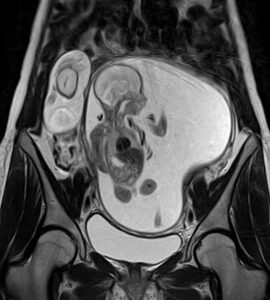

Ultrasound scans are crucial for diagnosing various medical conditions, and Dr Wadhwa Ultrasound CliniQ & Lab provides a full spectrum of services, including 3D/4D ultrasound services in Delhi. These advanced scans are ideal for prenatal assessments, giving expectant parents a detailed glimpse of their baby’s development. For those searching for a USG scan near me in Delhi, our clinic is a convenient choice for residents of Model Town, Ashok Vihar, Mukherjee Nagar, and other nearby areas.

Pregnancy is a delicate journey that requires precise monitoring. At our pregnancy ultrasound clinic in Delhi, we offer high-quality scans to ensure both maternal and foetal well-being. From routine check-ups to detailed anomaly scans, our expert radiologists are here to support you every step of the way. Families from Shalimar Bagh, Hudson Lane, and Rajouri Garden trust us for their pregnancy care needs.

- 3D/4D ultrasound services in Delhi: State-of-the-art imaging for detailed foetal scans.